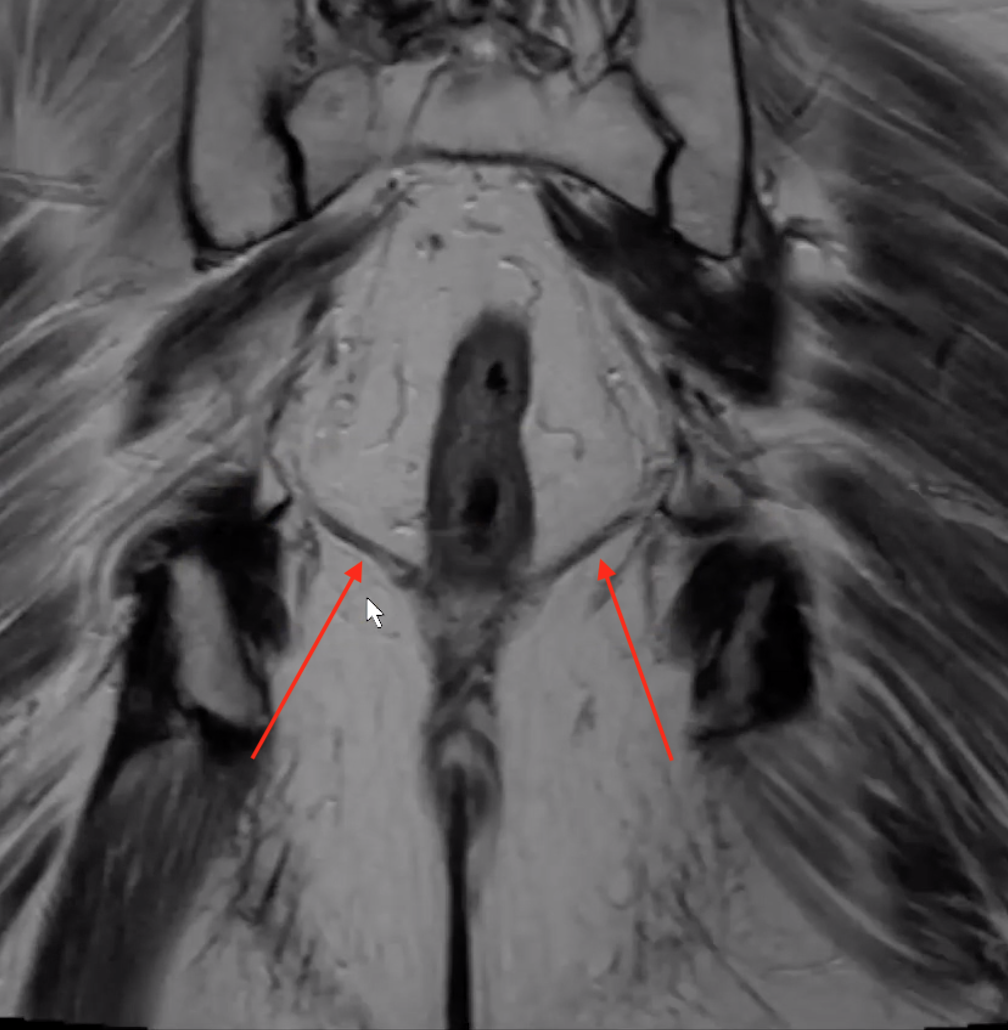

Anal Sphincters

• External sphincter

• Darker external line (blue)

• Extends slightly lower than internal

• Internal sphincter

• The brighter/white internal stuff (red)

Puborectalis

• U shaped muscle on either side